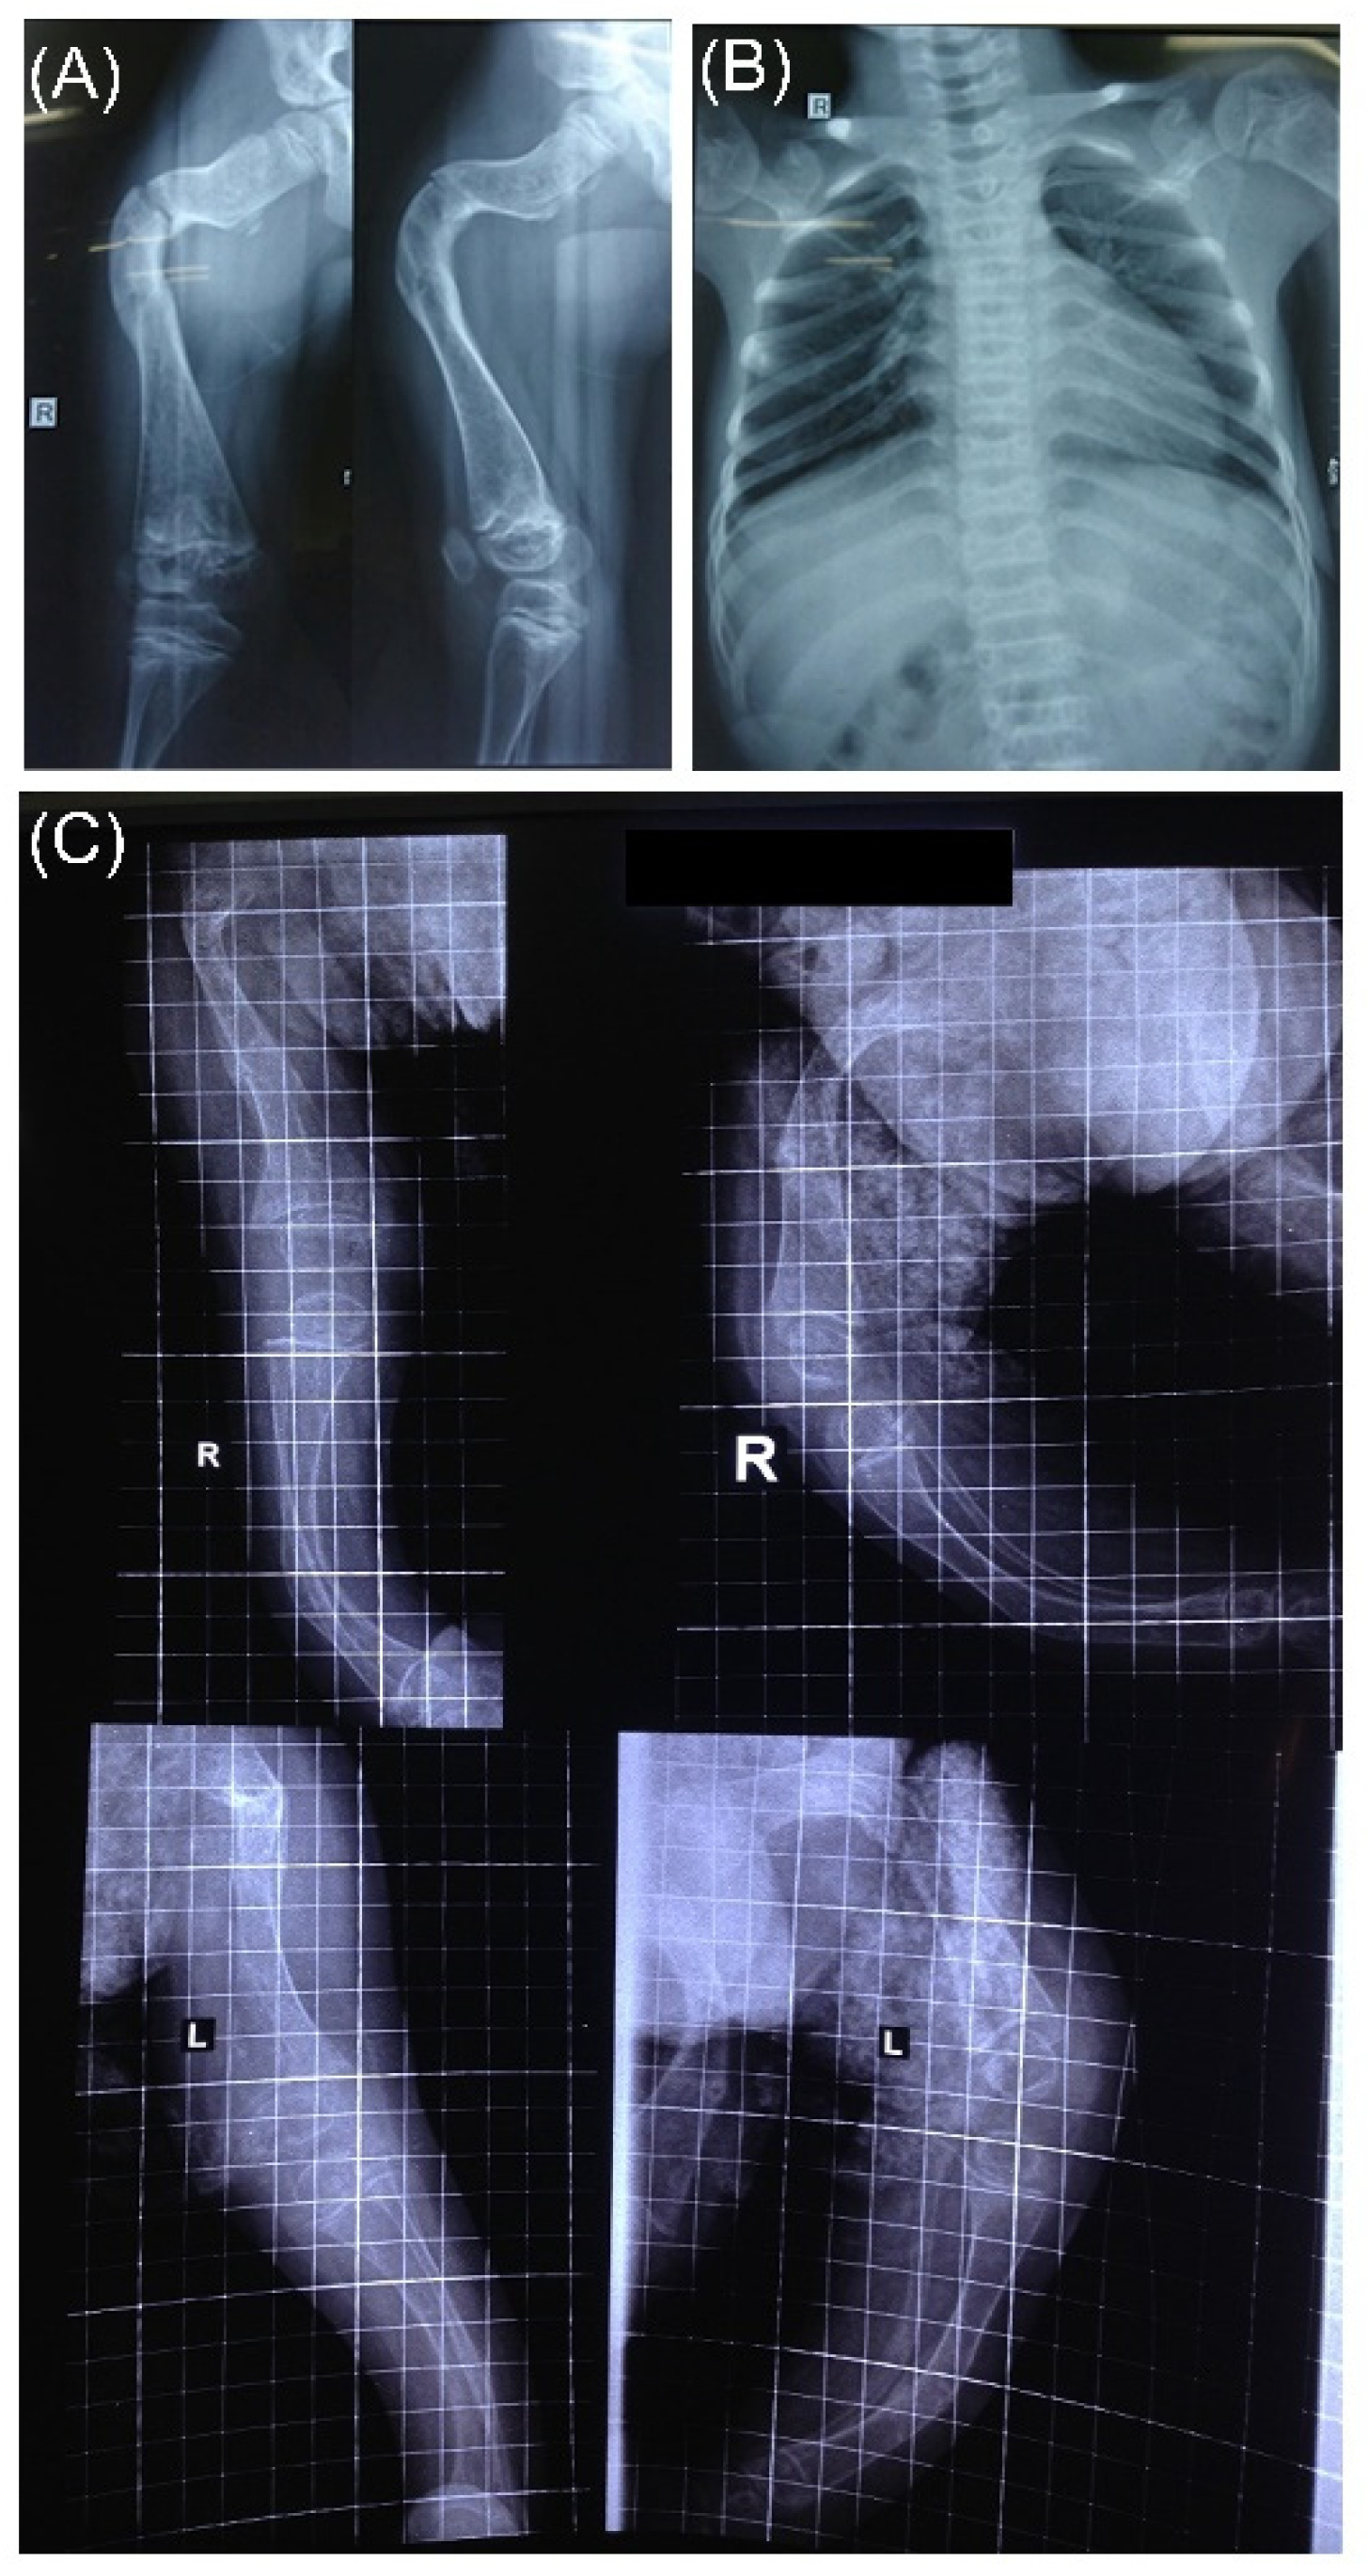

3.4. Radiographic Features